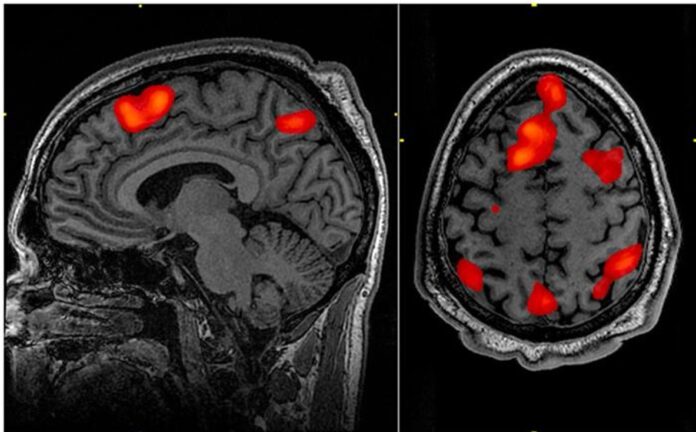

Bilim adamları ölmekte olan bir kişinin beyin aktivitesini ölmeden sadece 15 dakika önce kaydetti ve şaşırtıcı sonuçlar ortaya çıkardı.

Araştırmacılar, ölen kişinin beyninde, rüya görme ve meditasyon anına benzer “ritmik beyin dalgası kalıpları” buldu.

ABD’deki Louisville Üniversitesi’nde beyin cerrahı olan Dr Ajmal Zemmar, “Ölüm sırasındaki 900 saniyelik beyin aktivitesini ölçtük ve kalbin durmasından önceki ve sonraki 30 saniye içinde neler olduğunu araştırmak için özel bir odak belirledik” dedi.

Dr Zemmer, “Kalbin çalışmayı durdurmasından hemen önce ve sonra, gama salınımları olarak adlandırılan belirli bir sinirsel salınım bandında ve ayrıca delta, teta, alfa ve beta salınımları gibi diğerlerinde de değişiklikler gördük” dedi.

“Yaşlanma Nörobiliminde Sınırlar” da yayınlanan çalışma , “beynin ölüme geçiş sırasında ve hatta sonrasında aktif ve koordineli kalabileceğini ve hatta tüm çileyi düzenlemek için programlanabileceğini” söyledi.